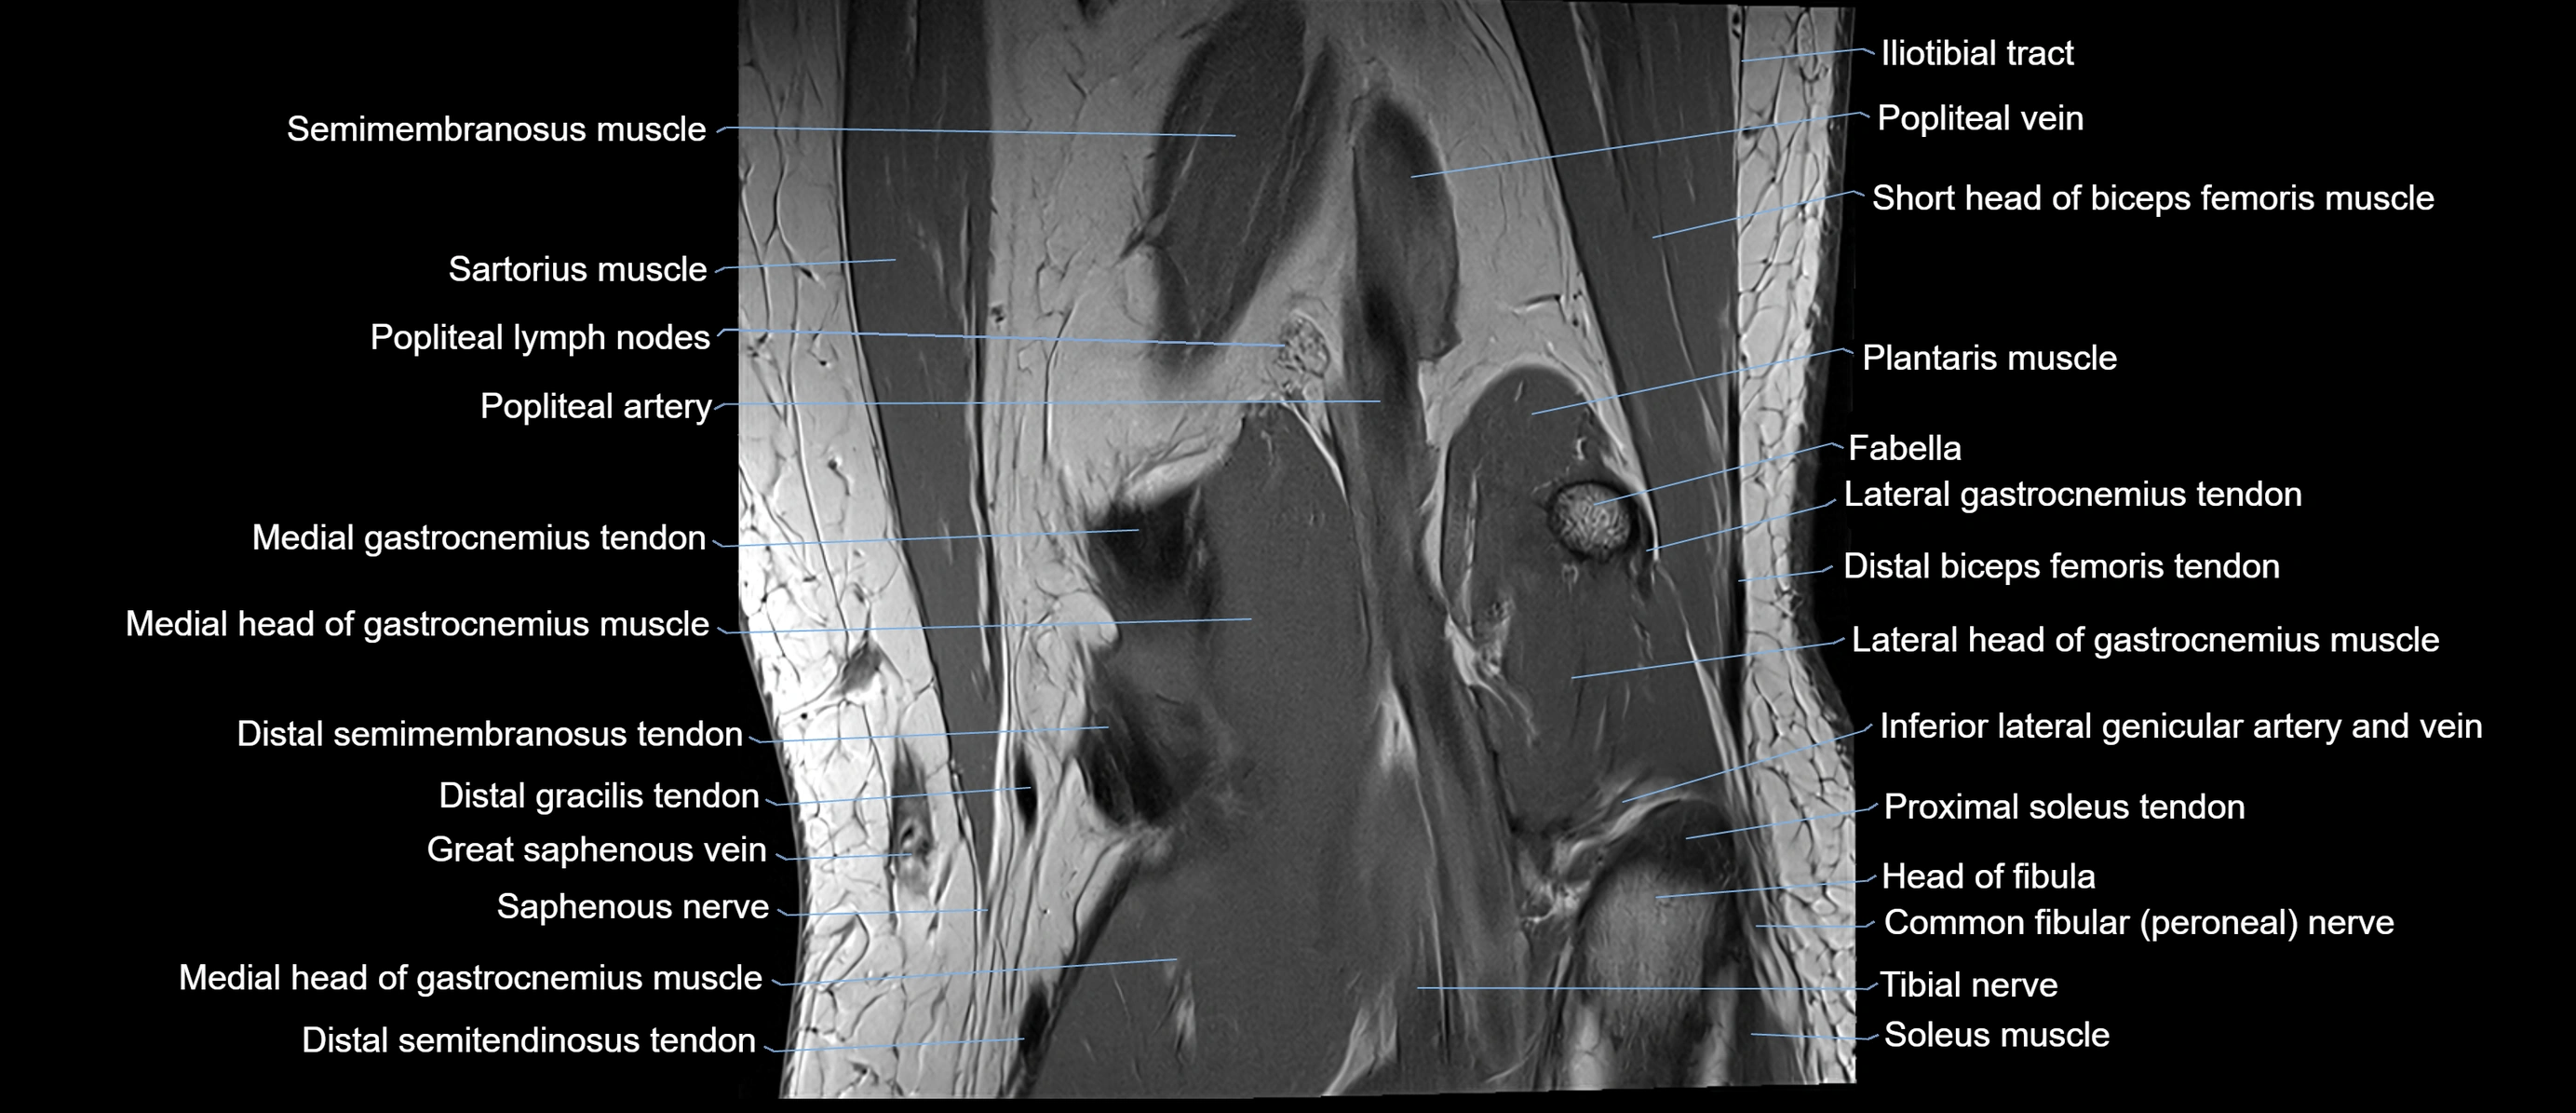

- Gastrocnemius muscle

- Head of fibula

- Lateral gastrocnemius tendon

- Lateral head of gastrocnemius muscle

- Medial gastrocnemius tendon

- Medial head of gastrocnemius muscle

- Neck of fibula

- Popliteal artery

- Popliteal lymph nodes

- Popliteal vein

- Semimembranosus muscle

- Soleus muscle

- Tibial nerve